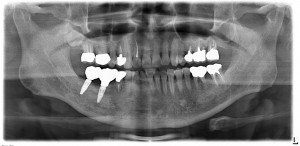

治療後のレントゲンです。インプラントにより快適な固定式の歯が入りました。